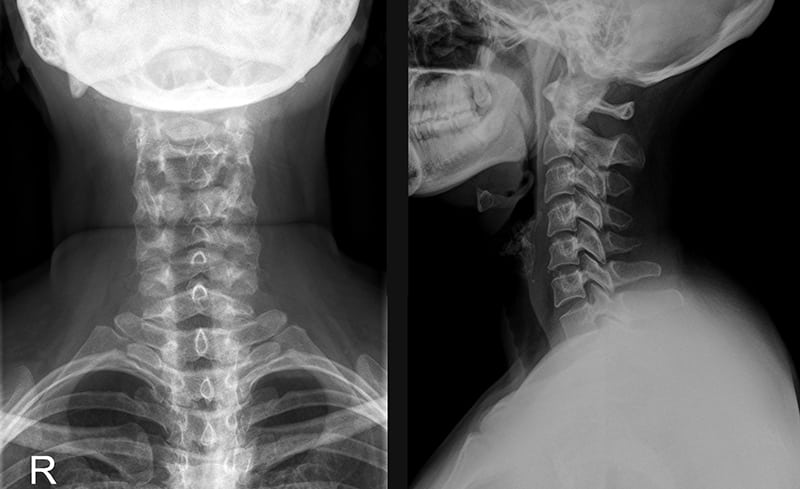

Первичный диагноз выставляется на основании жалоб пациентов и внешнего осмотра. Нормальное статическое положение шейных позвонков изменено — отмечается сглаживание физиологического лордоза, вынужденного положения головы, ограничение поворотов и наклонов. При пальпации обнаруживаются уплотнения, надавливание на которые приводит к появлению болезненных ощущений. Диаметр этих структур существенно разнится — от нескольких миллиметров до сантиметра, а иногда и более. Плотность образований, обычно локализованных в трапециевидной мышце, зависит от степени мышечных спазмов, стадии затронувших их фиброзных изменений.

Рентгенография используется для обнаружения деформации позвонков, разрастания костных тканей. С помощью этого исследования можно выявить аномалии позвоночника и последствия травмирования. МРТ и КТ проводятся для оценки состояния хрящевых тканей диска и степени сужения позвоночного канала. Эти диагностические мероприятия наиболее информативны при обнаружении грыж и новообразований.